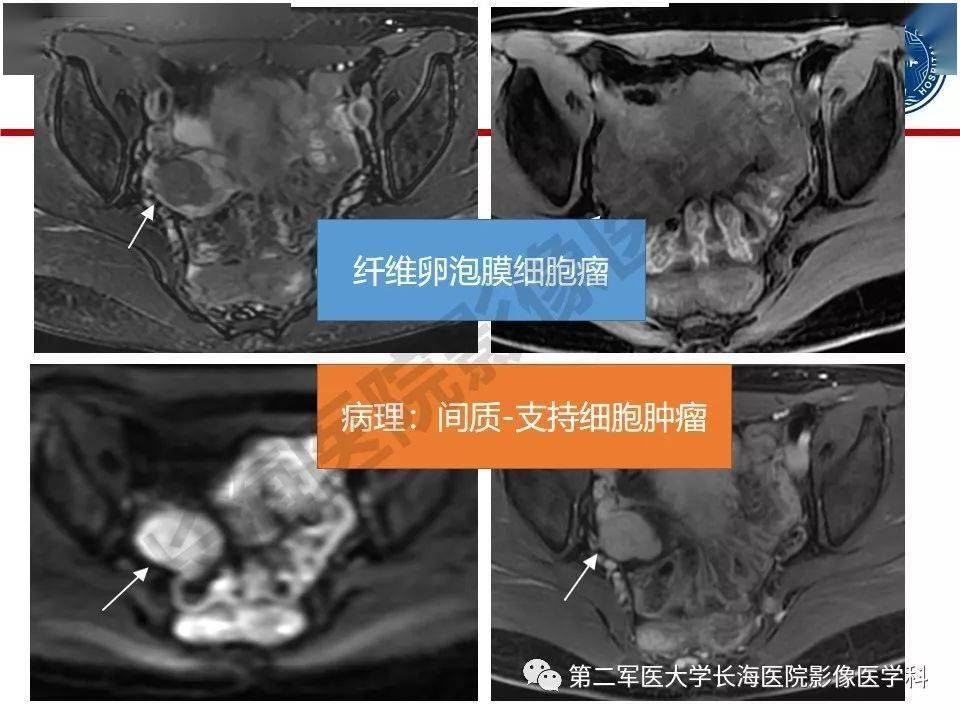

纤维卵泡膜细胞肿瘤影像诊断

图片尺寸960x720